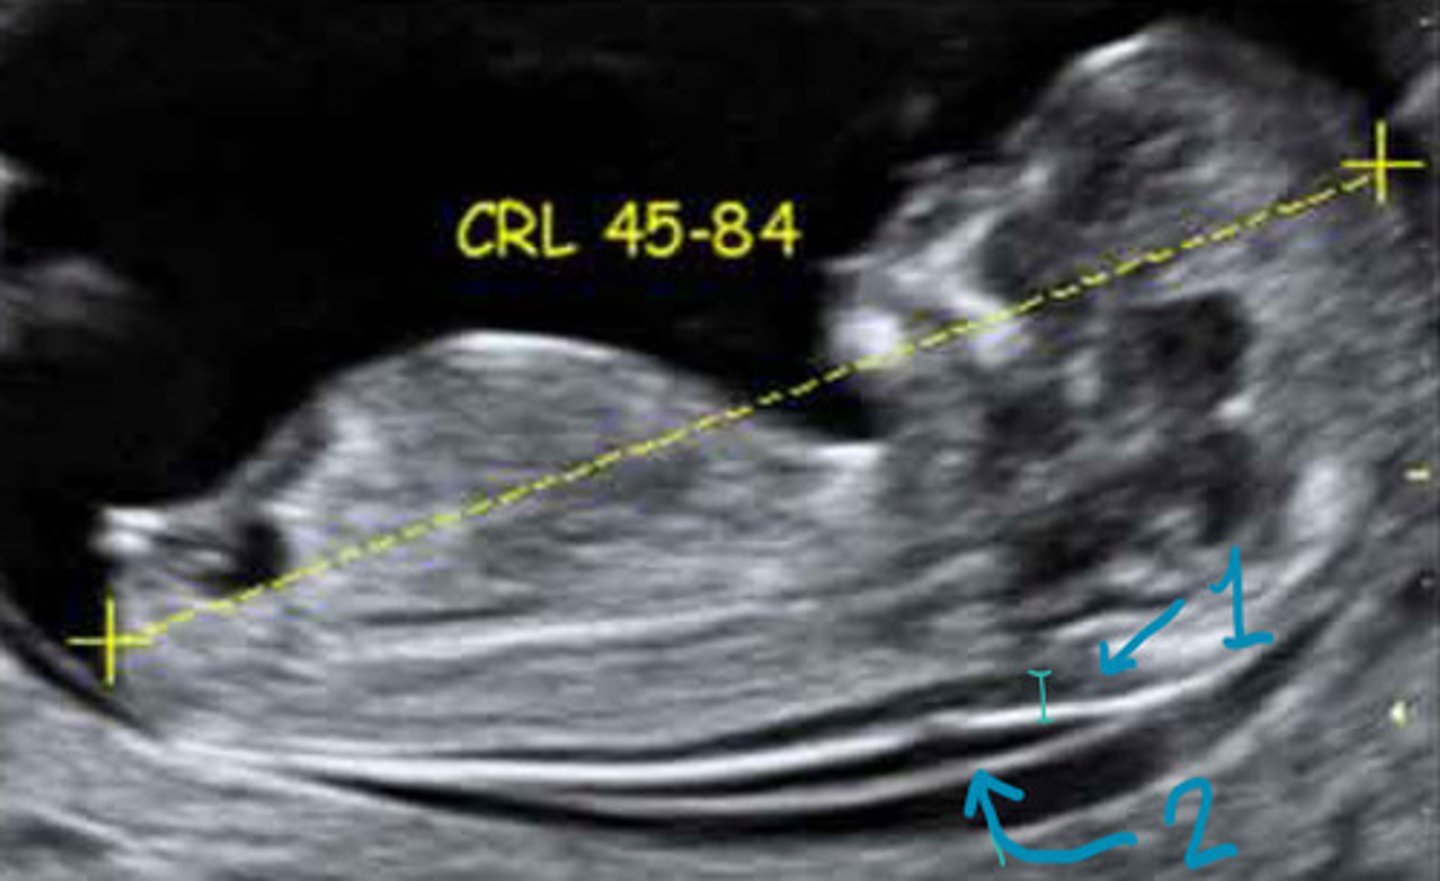

45-84mm

What must the CRL be for the NT scan

Gains turned down, widest translucency measured, neutral position

Describe the scanning technique for the NT

1

Which is the NT

NT

What is 1

Occipital bone

What is 2